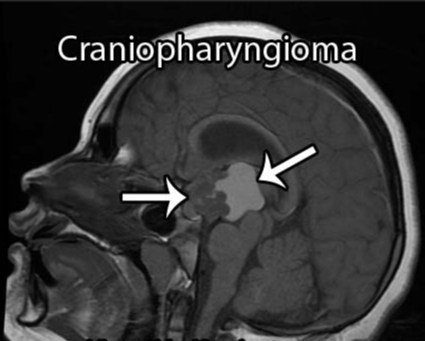

早在20世纪90年代,神经外科学奠基人Harvey Cushing便将颅咽管瘤定性为"最可怕的颅内肿瘤"。尽管其病理级别仅为WHO I级,发病率也低于垂体腺瘤,但低度恶性的病理分级并不等于临床处置的低难度——颅咽管瘤真正的挑战,根植于其解剖位置的高度复杂性。

肿瘤位于鞍区,紧邻垂体柄、下丘脑、视交叉及颅底重要血管结构,可操作的手术空间极为有限。术中对周围关键结构的任何扰动,都可能诱发严重的围手术期并发症,包括内分泌功能紊乱、视力损害、下丘脑损伤及脑脊液循环障碍等。加之确诊时肿瘤往往已生长至相当体积,手术全切难度极高,残留病灶的复发率亦显著偏高,患者术后须长期接受神经外科与内分泌专科的系统随访。时至今日,颅咽管瘤依然是儿童与成人群体中公认的最难处理的颅内肿瘤之一。

内镜还是开颅?颅咽管瘤应如何选择治疗方式

颅咽管瘤可沿垂体-下丘脑轴的任意位点发生并向该轴延伸,肿瘤可从蝶鞍延伸至大脑第三脑室,约50%的肿瘤起源于第三脑室底部漏斗和/或灰结节区域,主要朝第三脑室方向发展。患者可出现头痛、视力损害,以及由中枢性尿崩症引发的多饮多尿等症状;儿童患者可出现发育迟缓,成人则可表现为性功能障碍和下丘脑综合征(如体温调节紊乱、水电平衡失调)。

颅咽管瘤的起源部位决定了其周边的重要解剖结构,包括视神经、垂体柄、下丘脑,以及颈内动脉分支、基底动脉分支——尤其是基底动脉、后交通动脉和大脑后动脉与肿瘤的关系往往极为紧密,此外还涉及脑干等结构。视神经关系视力,垂体柄影响内分泌,下丘脑决定患者的认知能力和术后内分泌功能,脑干是人体"生命中枢",颈内动脉、基底动脉等大血管则统管全身血液运输。手术切除过程中一旦损伤上述重要结构,可能引发灾难性且不可逆的神经功能损害。